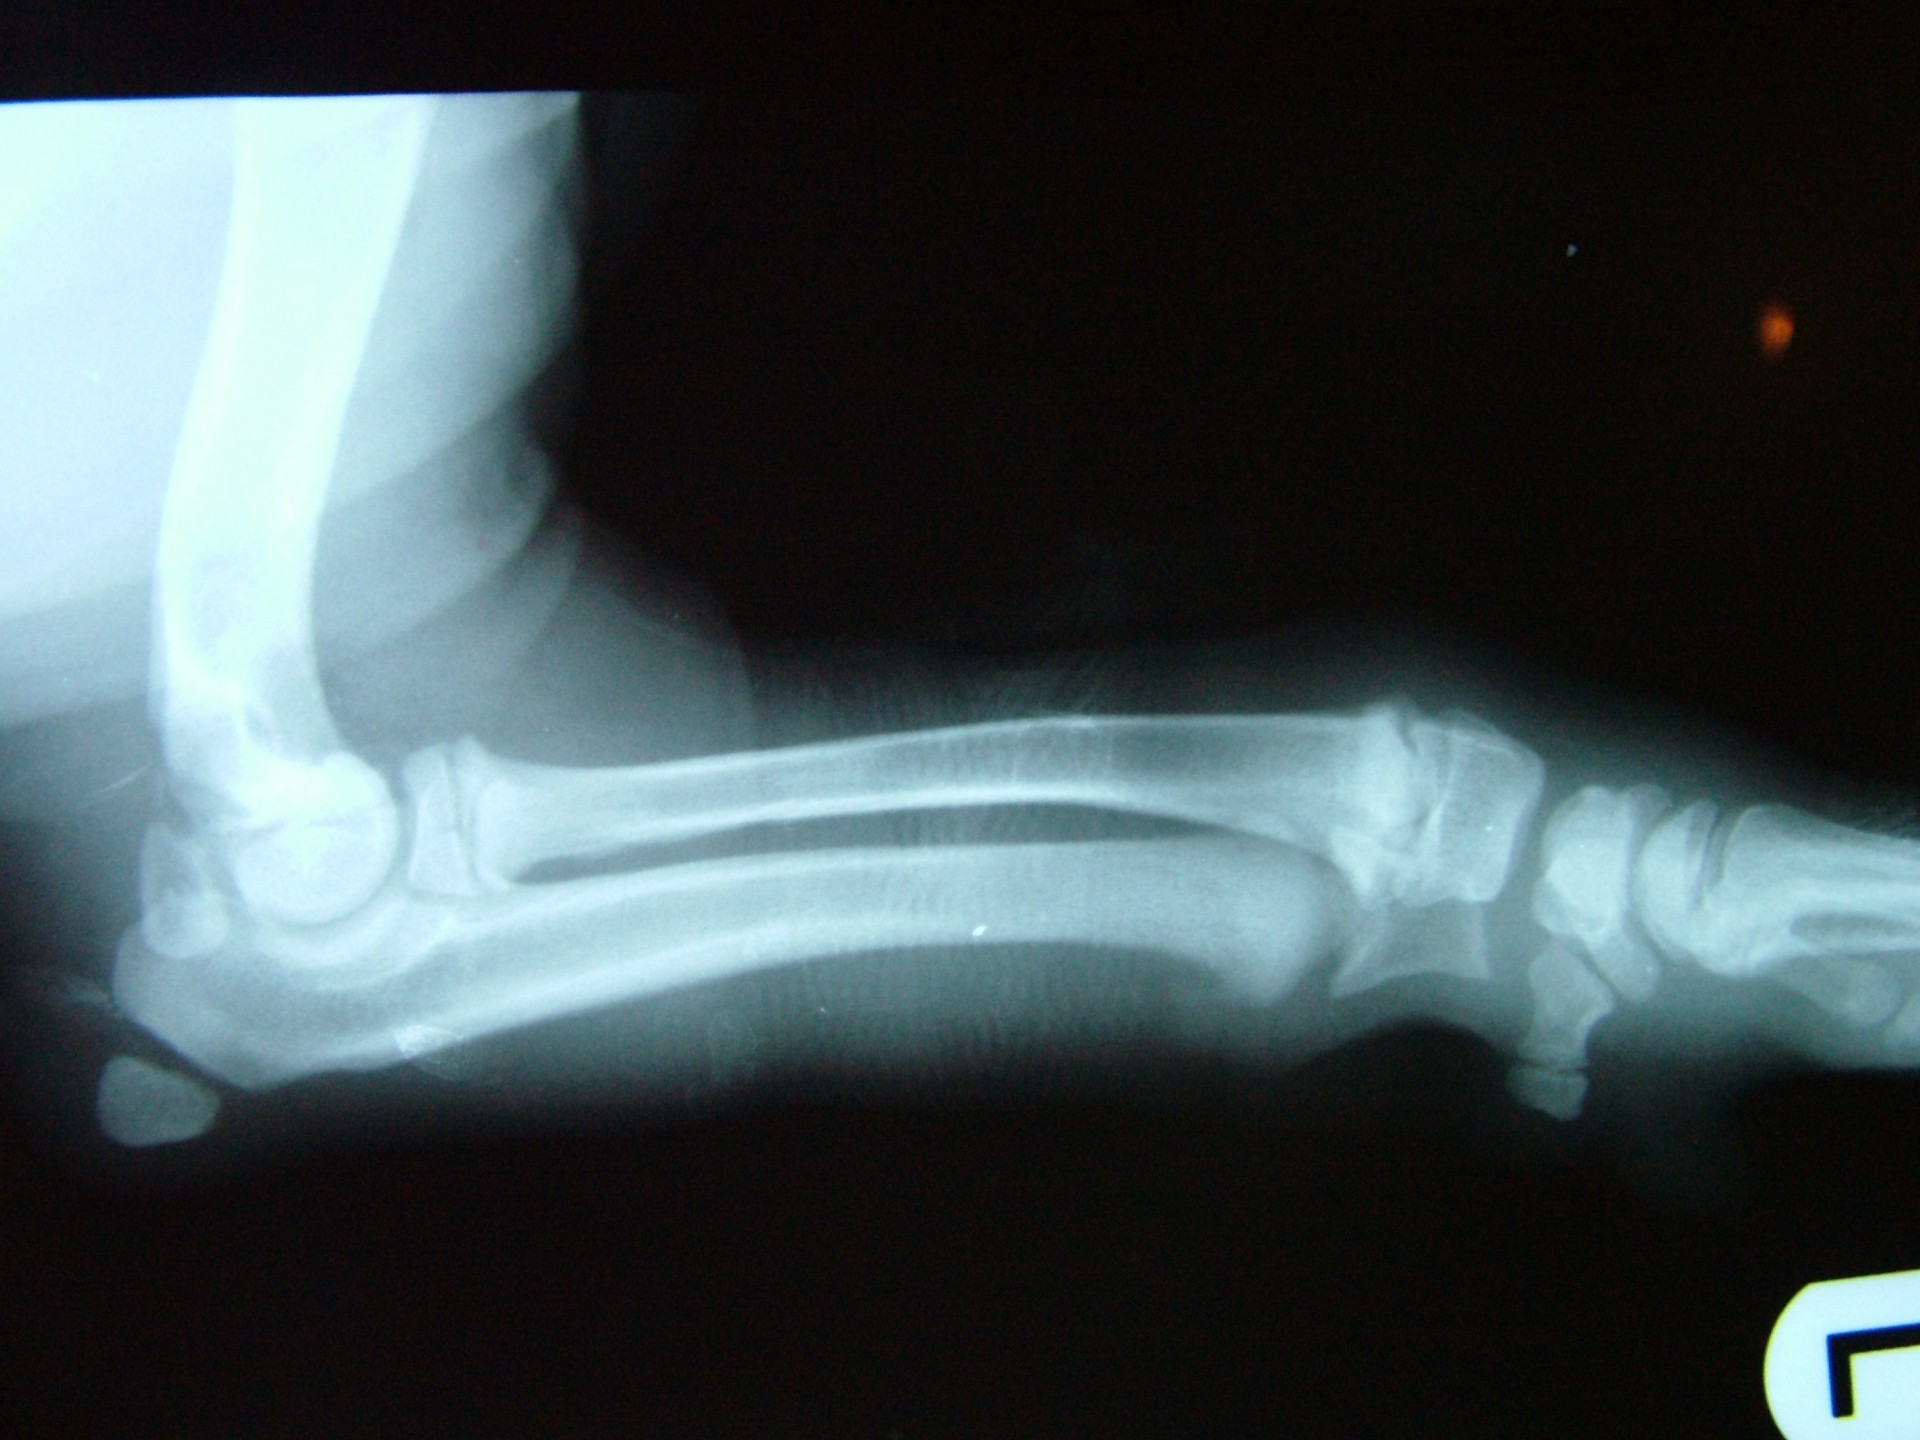

A betegségre jellemző, hogy az ébren klinikai tüneteket mutató állatok altatásban történő vizsgálata (az izmok ellazulása miatt)valamint az érintett végtagról készült röntgen vizsgálat mindig negatív eredménnyel zárul, a csontozatban rendellenesség nem mutatható ki.

A diagnózis felállítása során a legfontosabb, hogy kizárjuk a szintén fiatal állatokra jellemző, a csövescsontok növekedési zónájának lezáródásából adódó végtagdeformitást.